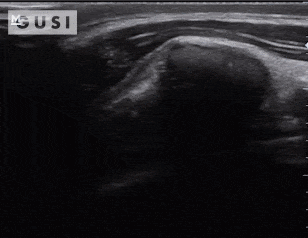

During the 2018 World Taekwondo Junior Championships in Hammamet, Tunisia, a 17-year-old male junior Taekwondo athlete took a fall, landing on his right shoulder. He exhibited a markedly limited range of motion in the affected shoulder and experienced intense pain, leading to suspicions of a dislocation.

A pre-reduction ultrasound (A) of the right shoulder showed a pronounced gap between the humeral head (indicated by a solid arrow) and the glenoid (marked by an open arrow), suggesting an anterior dislocation. Following a shoulder reduction procedure, a post-reduction ultrasound (B) verified the successful realignment of the glenohumeral joint (solid arrow pointing to the humeral head and open arrow to the glenoid).

After the procedure, the athlete displayed a considerably improved range of motion in his right shoulder and his pain levels diminished significantly.